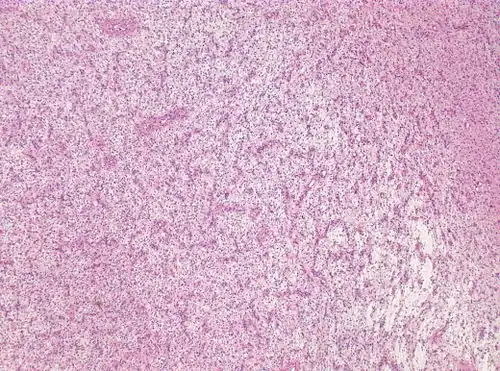

Photomicrograph displaying the AG tumor cells by histological evaluation, H&E stain. The striking characteristic of AG is that cells tend to cluster around brain blood vessels.[1]

Photomicrograph displaying the AG tumor cells by histological evaluation, H&E stain.Characteristics of AG: low Ki-67 proliferative rate, GFAP-positive, NeuN-positive, S-100-positive, Protein53-negative, Syn-negative, Olig-2-negative, CK-negative.[3]